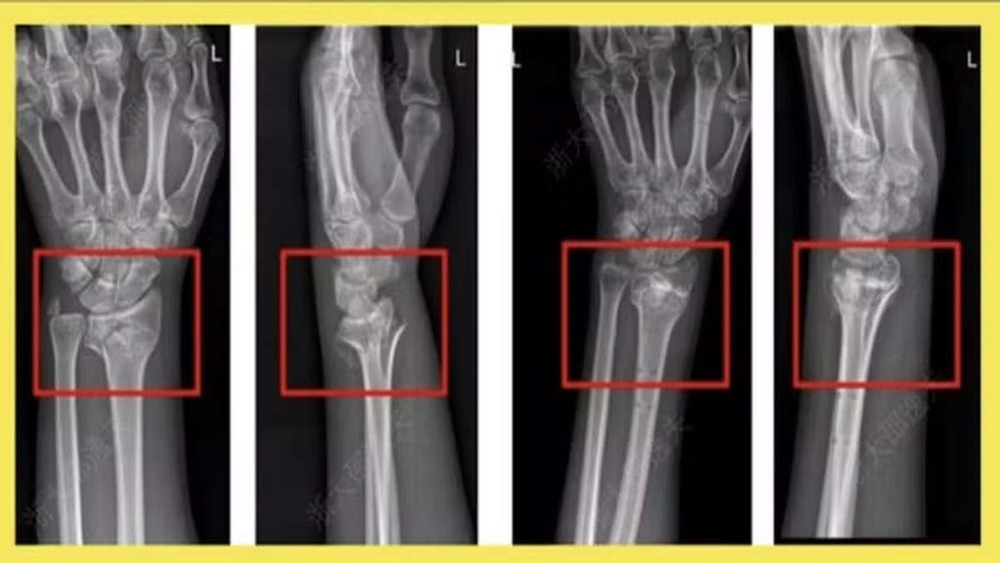

Aplicação com sucesso da Bone-02, a supercola óssea desenvolvida pela China — Foto: Reprodução

Aplicado por meio de injeção única, o material age como uma cola biocompatível que une fragmentos ósseos em três minutos. Em um caso experimental, um paciente com fratura no punho foi tratado com uma incisão de apenas 3 cm. O procedimento substituiu a necessidade de placa metálica e parafusos, além de eliminar uma possível segunda cirurgia para retirada dos implantes.

Após três meses de acompanhamento, a fratura estava totalmente cicatrizada e sem complicações. Outros 149 pacientes já receberam o tratamento, todos com resultados considerados positivos, de acordo com os relatos publicados no Global Times e no Cho Sun Daily.